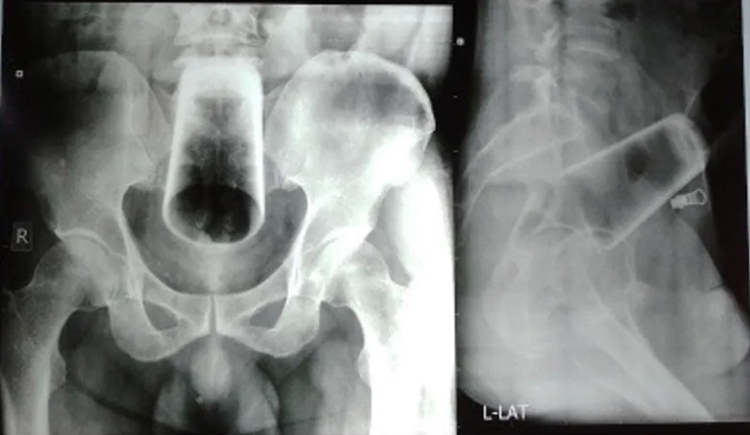

Um homem, de 47 anos, foi parar no hospital após passar 3 dias com um copo de vidro de 12cm enfiado no ânus após uma bebedeira. O caso aconteceu no Nepal e foi divulgado pelo Journal of Nepal Medical.

De acordo com a publicação, o homem chegou ao hospital se queixando de dores e contou que tinha um copo preso no ânus, alegando que o objeto havia ido parar ali após um acidente enquanto estava bêbado. Depois o paciente admitiu que introduziu o corpo para prazer sexual.

Para remover o objeto, a equipe médica precisou abrir o abdômen do homem, já que o copo estava preso no reto e não tinha como removê-lo por onde havia sido introduzido. Também foi necessário fazer uma incisão no intestino para conseguir mover o objeto diretamente. Após a cirurgia, o paciente ficou internado por uma semana e depois recebeu alta.